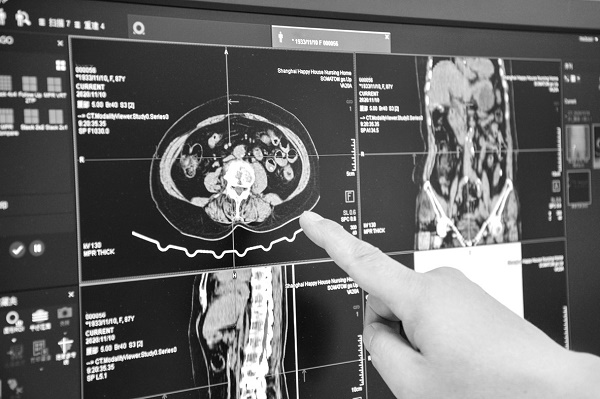

邯郸市级区域影像云平台覆盖市、县、乡三级医疗机构,将传统医疗影像检查与互联网、人工智能等高新技术相结合,基于医学影像数据的采集、传输、存储及智能分析等技术应用,为医生和患者提供数字影像服务、远程影像诊断服务、影像检查信息便捷查询服务,以及跨机构调阅共享服务、远程咨询服务等,促进优质医疗资源主动下沉,助力分级诊疗、双向转诊和城市医疗集团、县域医共体建设,提升邯郸市数字化医疗服务水平,推进城乡医疗卫生服务一体化、均等化、同质化。

截至2024年7月,邯郸市区域影像云平台覆盖该市各级医疗机构142家(其中二级及以上医疗机构40家,占邯郸市二级及以上医疗机构的87%),集中存储影像数据400万余条;已建成市、县两级影像诊断中心10家,注册医学影像科医生227人;39家二级及以上医疗机构已对接邯郸市影像云共享调阅系统,在保证信息安全的前提下,可同步提供数字影像服务和调阅跨医院就诊患者的影像信息,经测算,可为患者节约诊疗及相关费用数百万元。邯郸市推进数字化医疗改革,加强影像检查结果共享互认,提高了老百姓的就医获得感。

四是实现全市区域跨医疗机构调阅共享创新。云平台汇集了邯郸全市各级医疗机构影像数据,医生在院内通过邯郸市区域影像云共享调阅系统,就可以调阅患者在该市区域内其他医院的历史检查影像信息,实现全市影像数据跨县区与跨机构互联互通、共享调阅,有效辅助医生准确诊断患者病情,减少不必要的重复检查,大大提升了患者的就诊效率。